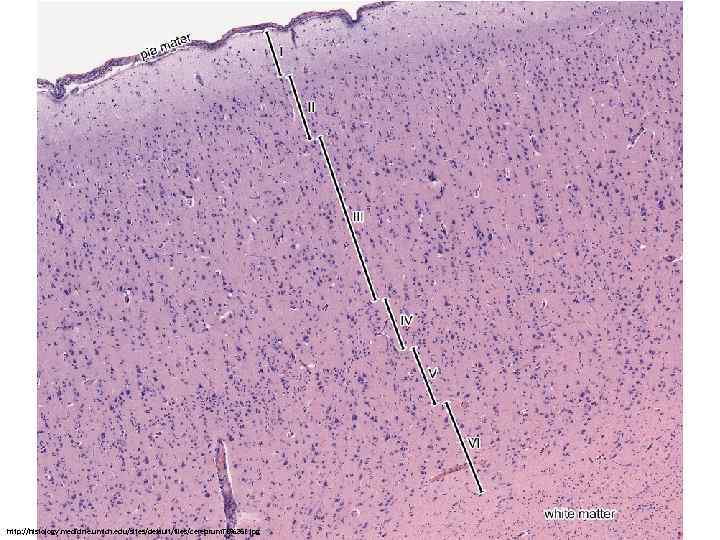

Нормальная гистология головного мозга Барановская Вера

http: //histology. medicine. umich. edu/sites/default/files/cerebrum. TB%26 E. jpg